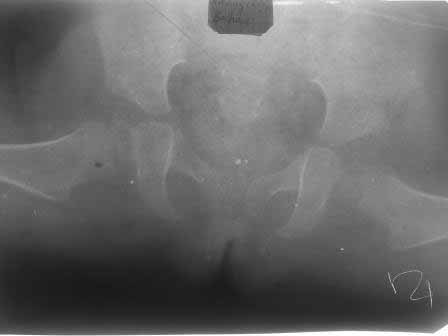

[Ortho] врожденный вивых бедра

через 9 месяцев после вправления